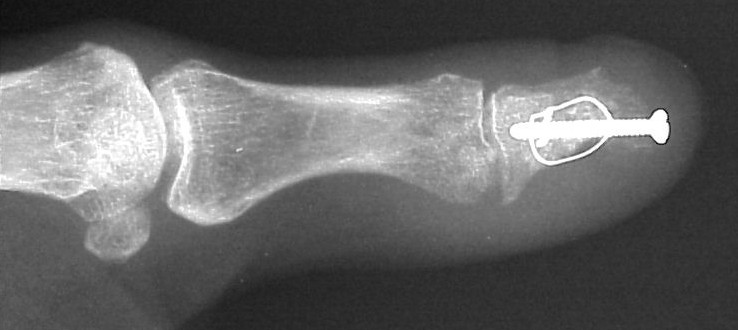

Exploration revealed no discrete  tumor, and a nondiagnostic frozen section. Because of diagnostic uncertainty and in order to avoid intraoperative cross contamination, a cancellous freeze dried allograft was used as a terminal graft:

This incorporated, with some terminal resorption: